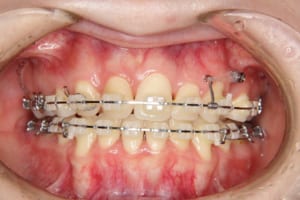

治療中

治療内容 唇側矯正装置を使用した成人矯正治療を行いました。

使用した装置 マルチブラケット装置(唇側矯正)

InVuブラケット

シルバーワイヤー

ホールディングアーチ

歯科矯正用アンカースクリュー(1本)

抜歯および非抜歯 上顎:右側中切歯、右側側切歯、左側第一小臼歯

下顎:両側第一小臼歯